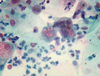

4

Q

A

4 Trichomonas vaginalis